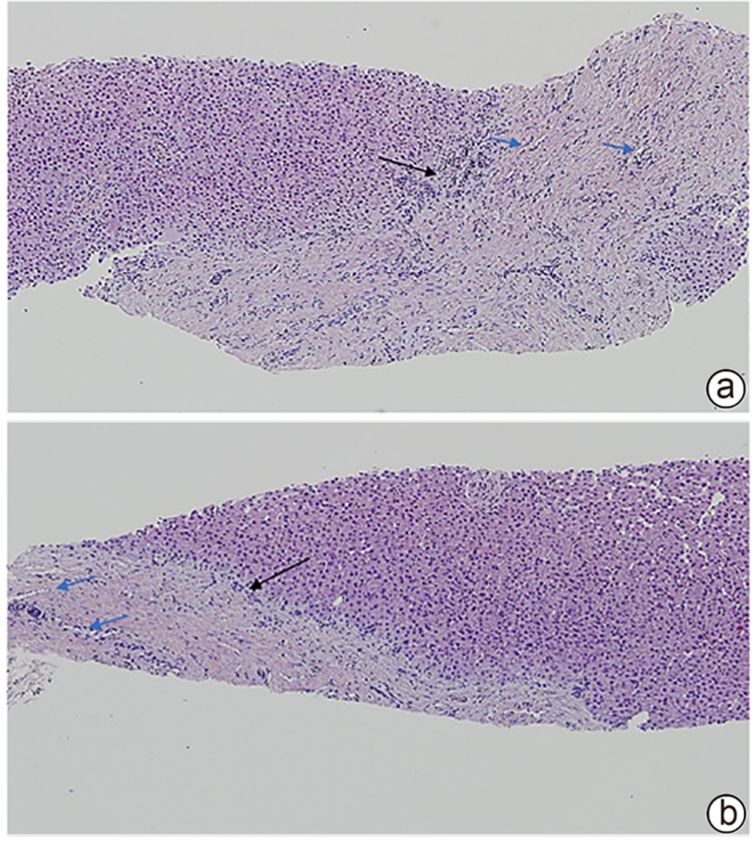

Clinical and pathological features of patients with congenital hepatic fibrosis: An analysis of 26 cases

Shixuan LIU, Yujiao ZHANG, Ying ZHENG, Aiping SONG, Tailing WANG, Xiuhong WANG

2025, 41(11): 2317-2322. DOI: 10.12449/JCH251118

Abstract(324) HTML (134) PDF (2080KB)(70)

Abstract:

Objectives  To summarize the clinical and pathological features of patients with congenital liver fibrosis (CHF), and to investigate the differences in clinical and pathological features between patients in different age groups.  Methods  A retrospective analysis was performed for the clinicopathological data of 26 patients with pathologically confirmed CHF in China-Japan Friendship Hospital from August 2005 to June 2023, and the patients were stratified by age to investigate the clinical and pathological features of patients in different age groups.  Results  Among the 26 patients, there were 12 male patients and 14 female patients, with an age of onset of 4 — 61 years. There were 19 patients with portal hypertension type (73.08%), 2 patients with cholangitis type (7.69%), 4 patients with mixed type (15.38%), and 1 patient with occult type (3.85%). Of all 26 patients, 4 had unknown clinical symptoms, and among the 22 patients with clear clinical symptoms, 10 (45.45%) attended the hospital due to upper gastrointestinal bleeding caused by portal hypertension. Pathological manifestations included roughly normal liver parenchyma separated by fibrous septa in the portal area, with the presence of abnormal reactive bile duct hyperplasia. Denser fibrous septa and a lack of portal veins with the corresponding caliber were observed in 4 pediatric patients with disease onset before the age of 10 years, with a significant reduction or even disappearance of compensatory thin-walled blood vessels.  Conclusion  Portal hypertension-type CHF is the most common type in clinical practice. Patients with an early age of onset have certain histopathological features of the liver, with the presence of serious complications associated with portal hypertension. Therefore, liver biopsy should be performed for patients suspected of CHF in clinical practice, and genetic testing should be performed when necessary. Early identification and diagnosis are of great importance for improving the prognosis of patients.